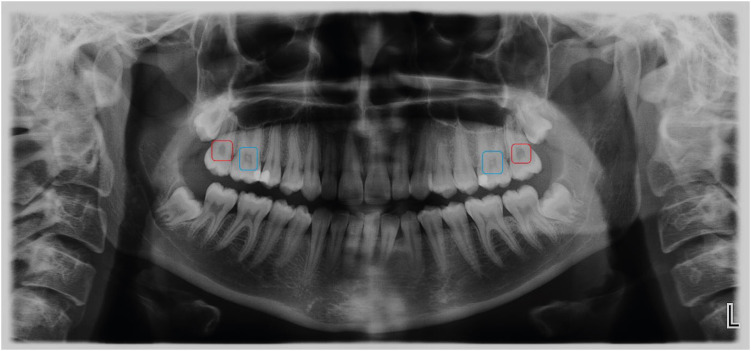

Materials and methods: Patients who were admitted to the Muğla Sıtkı Koçman University, Faculty of Dentistry, Department of Oral and Maxillofacial Radiology for dental complaints were registered. Among these patients, individuals who had routine biochemical tests at the same period in the Outpatient Clinics of Muğla Sıtkı Koçman University Training and Research Hospital were included in the study. The patients with at least 1 pulp stone on panoramic radiographs recorded as the "pulp stone group" while patients without any pulp stones were the "control group". Demographic data and serum levels of calcium, PTH, vitamin D, and uric acid were retrospectively evaluated in both groups. Student t-test or Mann-Whitney U test was used to evaluate the differences between the groups.

Abstract Image